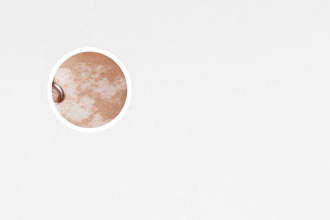

銀川地區(qū)治療白癜風(fēng)的醫(yī)院有很多,選擇哪家醫(yī)院“好一點(diǎn)”,需要綜合考慮醫(yī)院的資質(zhì)、設(shè)備、醫(yī)生水平、服務(wù)態(tài)度以及患者自身的情況等多方面因素。沒有一些“較好”的醫(yī)院,只有較適合您的醫(yī)院。 銀川哪個(gè)皮膚科醫(yī)院好一點(diǎn),這個(gè)問題沒有標(biāo)準(zhǔn)答案,關(guān)鍵在于選擇一家能夠提供專業(yè)、細(xì)致、個(gè)性化治療服務(wù)的醫(yī)院,并且與您的自身情況相匹配。選擇醫(yī)院前,建議多方了解,多咨詢,終做出適合自己的決定。 在選擇醫(yī)院的過程中,切勿盲目跟風(fēng),要理性分析,仔細(xì)斟酌,避免因?yàn)殄e(cuò)誤的選擇而延誤病情。下面,我們將從多個(gè)角度分析,幫助您更好地判斷銀川哪家皮膚科醫(yī)院更適合您。

白癜風(fēng)的治療需要借助多種科學(xué)的醫(yī)療設(shè)備,例如伍德燈、308準(zhǔn)分子激光、311窄譜UVB光療儀等。科學(xué)的設(shè)備能夠幫助醫(yī)生更精確地診斷病情,并制定更有效的治療方案。在選擇醫(yī)院時(shí),可以了解醫(yī)院擁有的醫(yī)療設(shè)備,并咨詢醫(yī)生這些設(shè)備的使用情況,以此判斷醫(yī)院的治療水平。